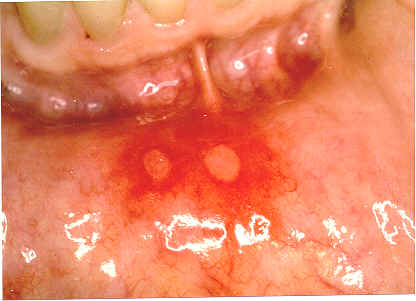

Herpes Pictures - Picture Aphthous Ulcers In The Mouth

This is a picture of aphthous ulcers which are often confused with cold sores, but they are not caused by the herpes virus. Apthous ulcers can occur anywhere in the mouth but do not involve the outside of the lip. ... Read Article